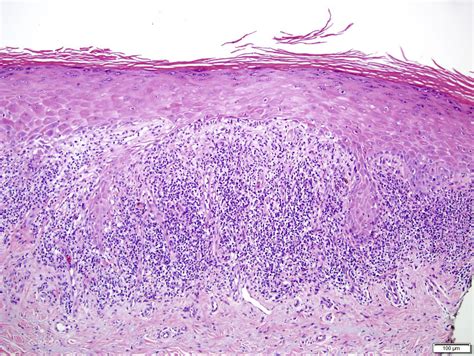

At its core, Erosive Lichen Planus is an autoimmune inflammatory condition. While the exact cause remains unknown, it occurs when the body's immune system mistakenly attacks the lining cells of the mucous membranes. This persistent inflammation leads to the breakdown of the tissue, resulting in painful, red, and eroded areas that are often rimmed with white, radiating lines known as Wickham striae. Because it is a chronic condition, patients often experience periods of remission followed by painful flares.

Identifying the condition early is vital, as the chronic inflammation and constant cell turnover associated with this form have been linked, in rare instances, to an increased risk of oral cancer. Therefore, consistent monitoring by a dental professional or an oral medicine specialist is non-negotiable for those diagnosed with the condition.